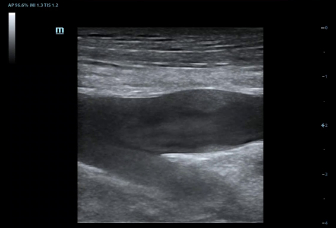

–£–Ϋ–Β–¥―Ä–Β–Ϋ–Η–Β –≤ DC-80 EXP –¥–Α―²―΅–Η–Κ–Ψ–≤ ―¹–≤–Β―Ä―Ö–≤―΄―¹–Ψ–Κ–Ψ–Ι –Ω―Ä–Ψ–Η–Ζ–≤–Ψ–¥–Η―²–Β–Μ―¨–Ϋ–Ψ―¹―²–Η –Ψ–±–Β―¹–Ω–Β―΅–Η–≤–Α–Β―² –¥–Μ―è –£–Α―¹ –Ω―Ä–Β–≤–Ψ―¹―Ö–Ψ–¥–Ϋ–Ψ–Β –Κ–Α―΅–Β―¹―²–≤–Ψ –≤–Η–Ζ―É–Α–Μ–Η–Ζ–Α―Ü–Η–Η.

–Θ–Μ―¨―²―Ä–Α–Μ–Β–≥–Κ–Η–Ι –Η –≤―΄―¹–Ψ–Κ–Ψ–Ω–Μ–Ψ―²–Ϋ―΄–Ι –Ψ–±―ä–Β–Φ–Ϋ―΄–Ι –¥–Α―²―΅–Η–Κ –Ψ–±–Β―¹–Ω–Β―΅–Η–≤–Α–Β―² –Ω―Ä–Β–≤–Ψ―¹―Ö–Ψ–¥–Ϋ–Ψ–Β –Κ–Α―΅–Β―¹―²–≤–Ψ –≤–Η–Ζ―É–Α–Μ–Η–Ζ–Α―Ü–Η–Η –≤ –Α–Κ―É―à–Β―Ä―¹―²–≤–Β –≤ ―Ä–Β–Ε–Η–Φ–Α―Ö 2D, –Π–î–ö, 3D/4D –¥–Μ―è –±–Ψ–Μ―¨―à–Β–Ι –¥–Η–Α–≥–Ϋ–Ψ―¹―²–Η―΅–Β―¹–Κ–Ψ–Ι ―É–≤–Β―Ä–Β–Ϋ–Ϋ–Ψ―¹―²–Η –Η –Ω–Ψ–≤―΄―à–Β–Ϋ–Η―è –Κ–Α―΅–Β―¹―²–≤–Α –Η―¹―¹–Μ–Β–¥–Ψ–≤–Α–Ϋ–Η―è;

–Γ–Ω–Β―Ü–Η–Α–Μ―¨–Ϋ–Ψ ―¹–Κ–Ψ–Ϋ―¹―²―Ä―É–Η―Ä–Ψ–≤–Α–Ϋ–Ϋ―΄–Ι –¥–Α―²―΅–Η–Κ –¥–Μ―è –Ω―Ä–Ψ–≤–Β–¥–Β–Ϋ–Η―è –Η–Ϋ–≤–Α–Ζ–Η–≤–Ϋ―΄―Ö –Ω―Ä–Ψ―Ü–Β–¥―É―Ä –Η –Η―¹―¹–Μ–Β–¥–Ψ–≤–Α–Ϋ–Η–Ι –≤ 2D ―¹ –Φ–Η–Ϋ–Η–Φ–Α–Μ―¨–Ϋ–Ψ–Ι ―¹–Μ–Β–Ω–Ψ–Ι –Ζ–Ψ–Ϋ–Ψ–Ι, –Α ―²–Α–Κ–Ε–Β –Κ–Ψ–Ϋ―²―Ä–Α―¹―²-―É―¹–Η–Μ–Β–Ϋ–Ϋ―΄―Ö –Η―¹―¹–Μ–Β–¥–Ψ–≤–Α–Ϋ–Η–Ι;

–ï–≥–Ψ –Κ–Ψ―Ä–Ω―É―¹ ―É–¥–Ψ–±–Ϋ–Ψ ―Ä–Α–Ζ–Φ–Β―â–Α–Β―²―¹―è –≤ ―Ä―É–Κ–Β –Η –Ω–Ψ–¥–¥–Β―Ä–Ε–Η–≤–Α–Β―² –Ω―Ä–Η–Φ–Β–Ϋ–Β–Ϋ–Η–Β ―¹–Ω–Β―Ü–Η–Α–Μ–Η–Ζ–Η―Ä–Ψ–≤–Α–Ϋ–Ϋ–Ψ–Ι –±–Η–Ψ–Ω―¹–Η–Ι–Ϋ–Ψ–Ι –Ϋ–Α―¹–Α–¥–Κ–Η ―¹ –Ω–Ψ–Κ―Ä―΄―²–Η–Β–Φ –Η–Ζ –Ϋ–Α–Ϋ–Ψ–Φ–Α―²–Β―Ä–Η–Α–Μ–Α –¥–Μ―è –Μ–Β–≥–Κ–Ψ–Ι –¥–Β–Ζ–Η–Ϋ―³–Β–Κ―Ü–Η–Η.